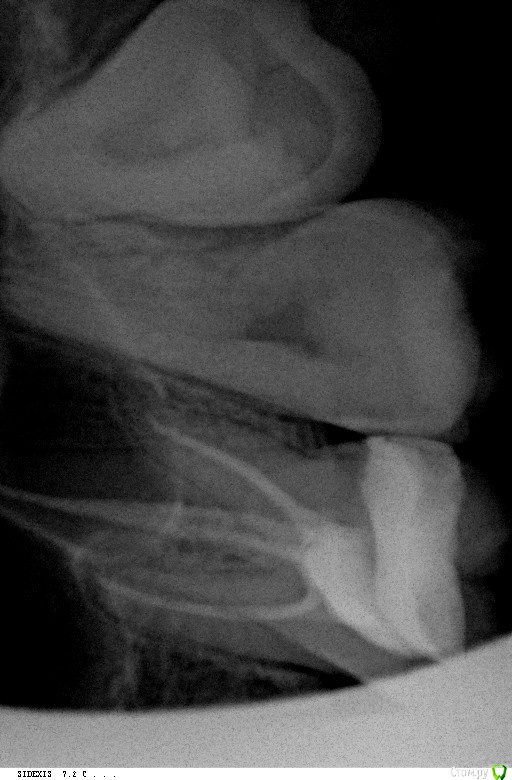

Yulia_yulia Опубликовано 1 февраля, 2017 Поделиться Опубликовано 1 февраля, 2017 Здравствуйте! Проблема: 26 зуб верхний несколько раз пломбировался (кусочек отваливался один раз). Неделю назад из-за виноградной косточки откололась снова небольшая часть и появилась дырка (видно черное пятно внутри зуба). Один день после откола было больно есть (при попадании еды внутрь дырки), сейчас норм. Не болит. На консультации сделали рентген. Врач сказал, надо чистить каналы, так как есть киста + ставить коронку и еще делать томографию этого зуба. Цена вопроса 50 тыс. руб. Для меня это сейчас очень дорого (нужно пломбы и на других зубах еще менять). Подскажите, пожалуйста, действительно в данном случае необходима коронка и чистка каналов? Или безопасно будет и пломбу поставить (или керамическую вкладку)? Если есть киста, то обязательна эта чистка? Ссылка на комментарий

St. Опубликовано 2 февраля, 2017 Поделиться Опубликовано 2 февраля, 2017 Если поставить пломбу, есть риск что снова что-то отколется, а на какую глубину и когда никто не знает. Если откалывается глубоко под десну - зуб приходится удалять. Опять же, хорошо что сейчас зуб не болит, но поскольку там есть хроническое воспаление ( то что назвали "киста") оно само по себе не пройдет и когда-то может разболеться.Т.е. все равно к лечению этого зуба придется возвращаться. 1 Ссылка на комментарий

Ирина Игоревна Опубликовано 2 февраля, 2017 Поделиться Опубликовано 2 февраля, 2017 Причиной воспаления (кисты) является инфекция в каналах, чтобы её убрать их нужно перелечить, так что без чистки каналов не обойтись. 1 Ссылка на комментарий